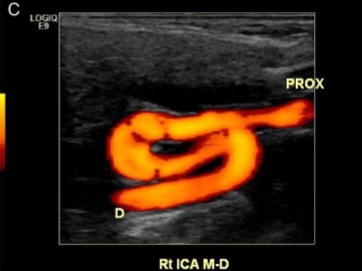

What kind of limitation to a carotid exam is seen here?

Course of a vessel (tortuous)